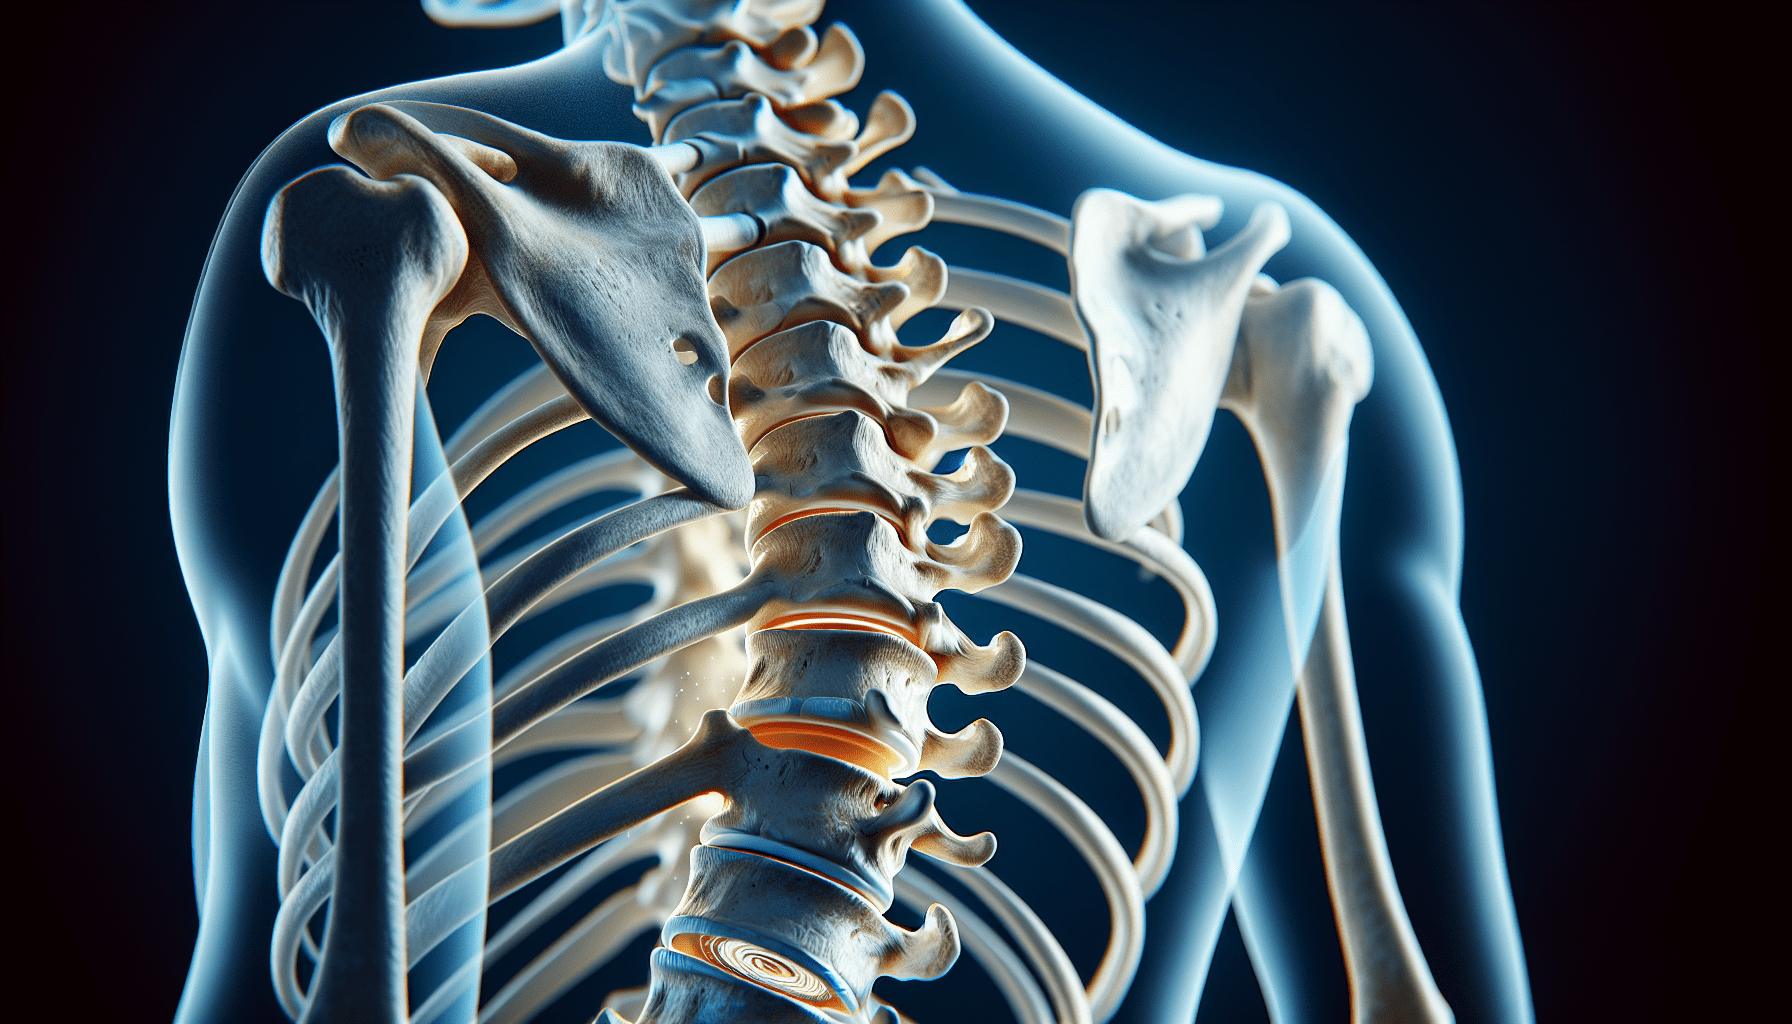

Disc protrusion, also known as a herniated disc, occurs when the soft inner core of a spinal disc pushes through the tough outer layer. This can result in pain, numbness, tingling, or weakness in the areas affected by the affected nerve. Disc protrusion can be caused by degenerative changes, repetitive stress, or sudden traumatic injuries.

Your Discs Are Like Cushions Between Your Vertebrae

Imagine your spinal discs as cushions that sit between each vertebra, absorbing shock and enabling movement. When a disc protrudes, it can compress nearby nerves and cause symptoms like pain or weakness. Spinal instability can increase the likelihood of disc protrusion due to the abnormal stresses placed on the discs.